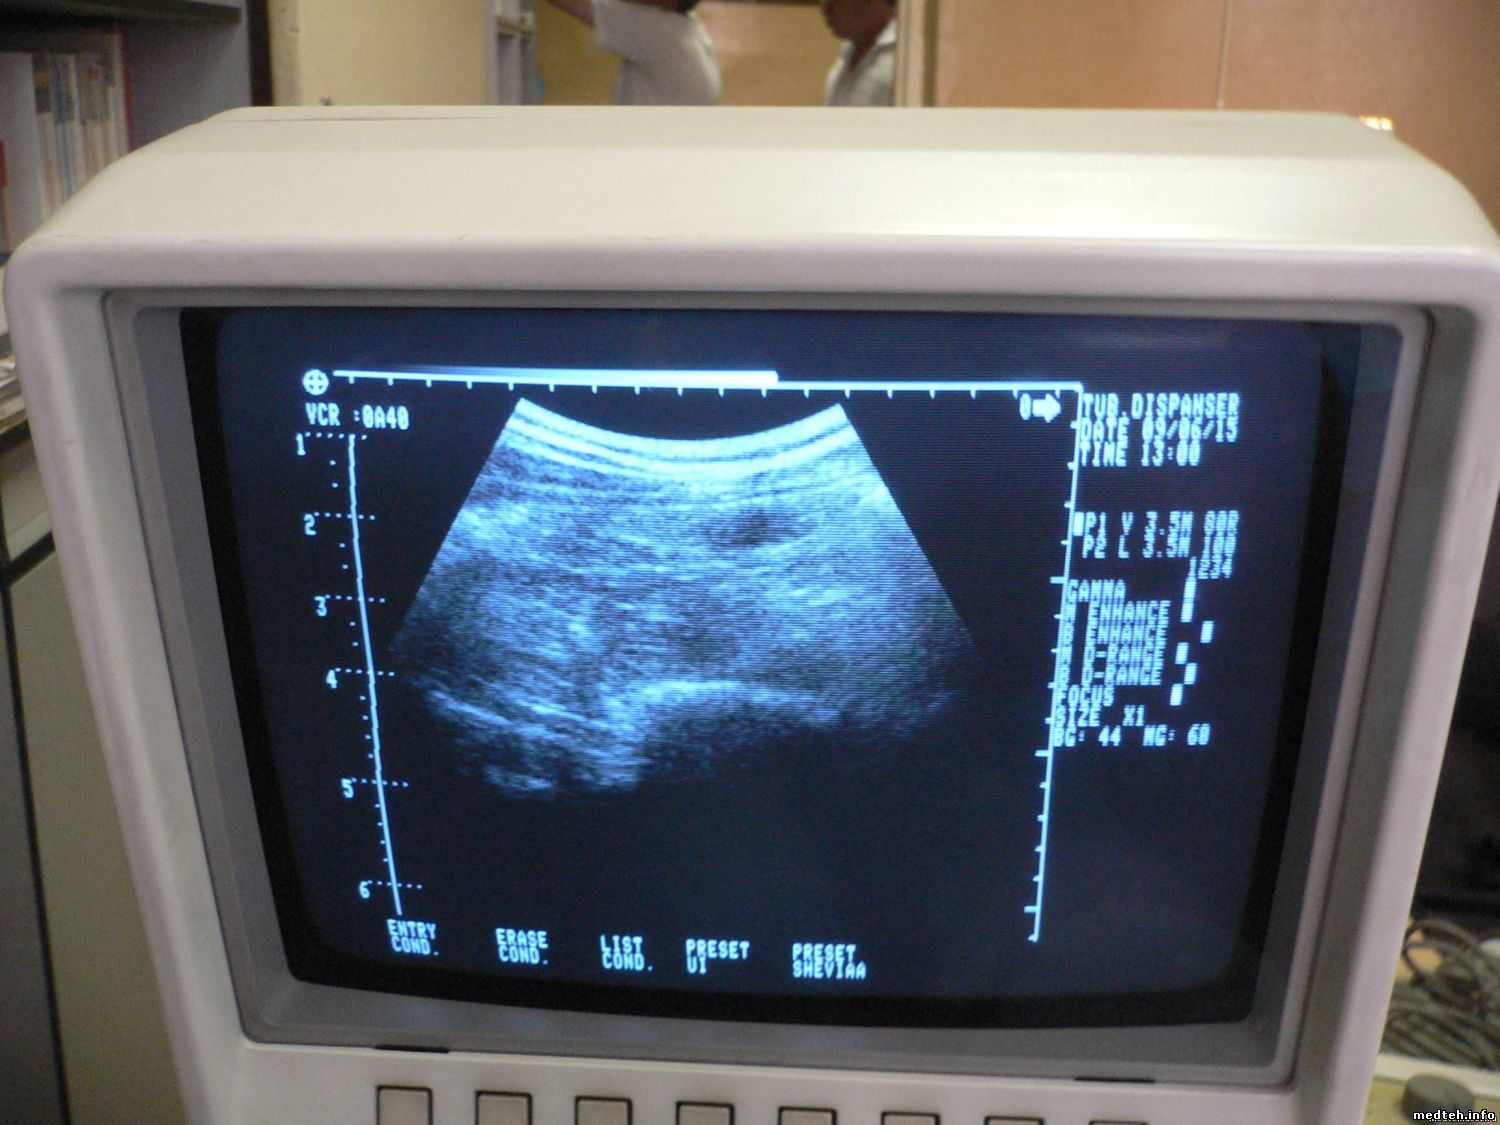

итак начнем сначала. прибор приехал с неисправностью: после 1 - 2 часов работы пропадет сектор. то, что на экране была зебра - это одно из плат rdly не была вставлена до конца. что имеем при включении см. фото 1:

если сканировать живот с гелем видно это см. фото 2:

непонятно почему нет низа картинки ... если прислонить излучатель к металлу низ сразу появляется очень четко .

Картинка на животе хорошая. С металлом ты получаешь жеский отраженный сигнал и видишь не глубину а забитый датчик, это не хорошо для кристаллов. Теперь определяйся что у тебя пропадает через 1-2 часа, эхо или излучение. Чтобы посмотреть четкость картинки в полевых условиях, в кусок хозяйственного мыла я загоняю две выровняные скрепки, одну примерно посредине другую перпендикулярно,